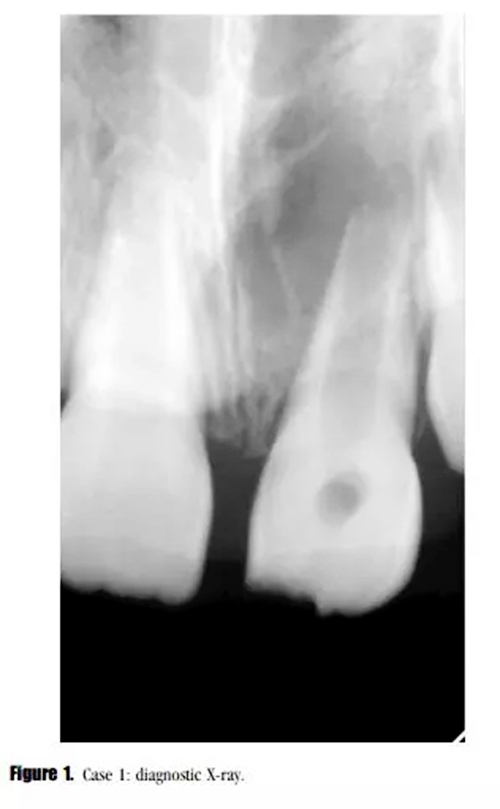

主訴:左上恒中切牙腫脹。(圖1)

影像學(xué)檢查: X線顯示,21根尖發(fā)育達(dá)到第三階段,根尖區(qū)被大面積低密度透射影像包繞。患牙被診斷為慢性根尖周炎急性發(fā)作。

在3,6,9個(gè)月的隨后跟蹤隨訪中,患者完全沒有癥狀。與鄰牙和對(duì)側(cè)牙對(duì)比,21的叩診、捫診以及牙周袋深度都在正常范圍內(nèi)。對(duì)于牙髓溫度測(cè)試沒有反應(yīng)。影像學(xué)評(píng)估顯示,根尖區(qū)低密度透射影像范圍減小,牙根發(fā)育為I型(按照Chueh等人的研究)(圖2),